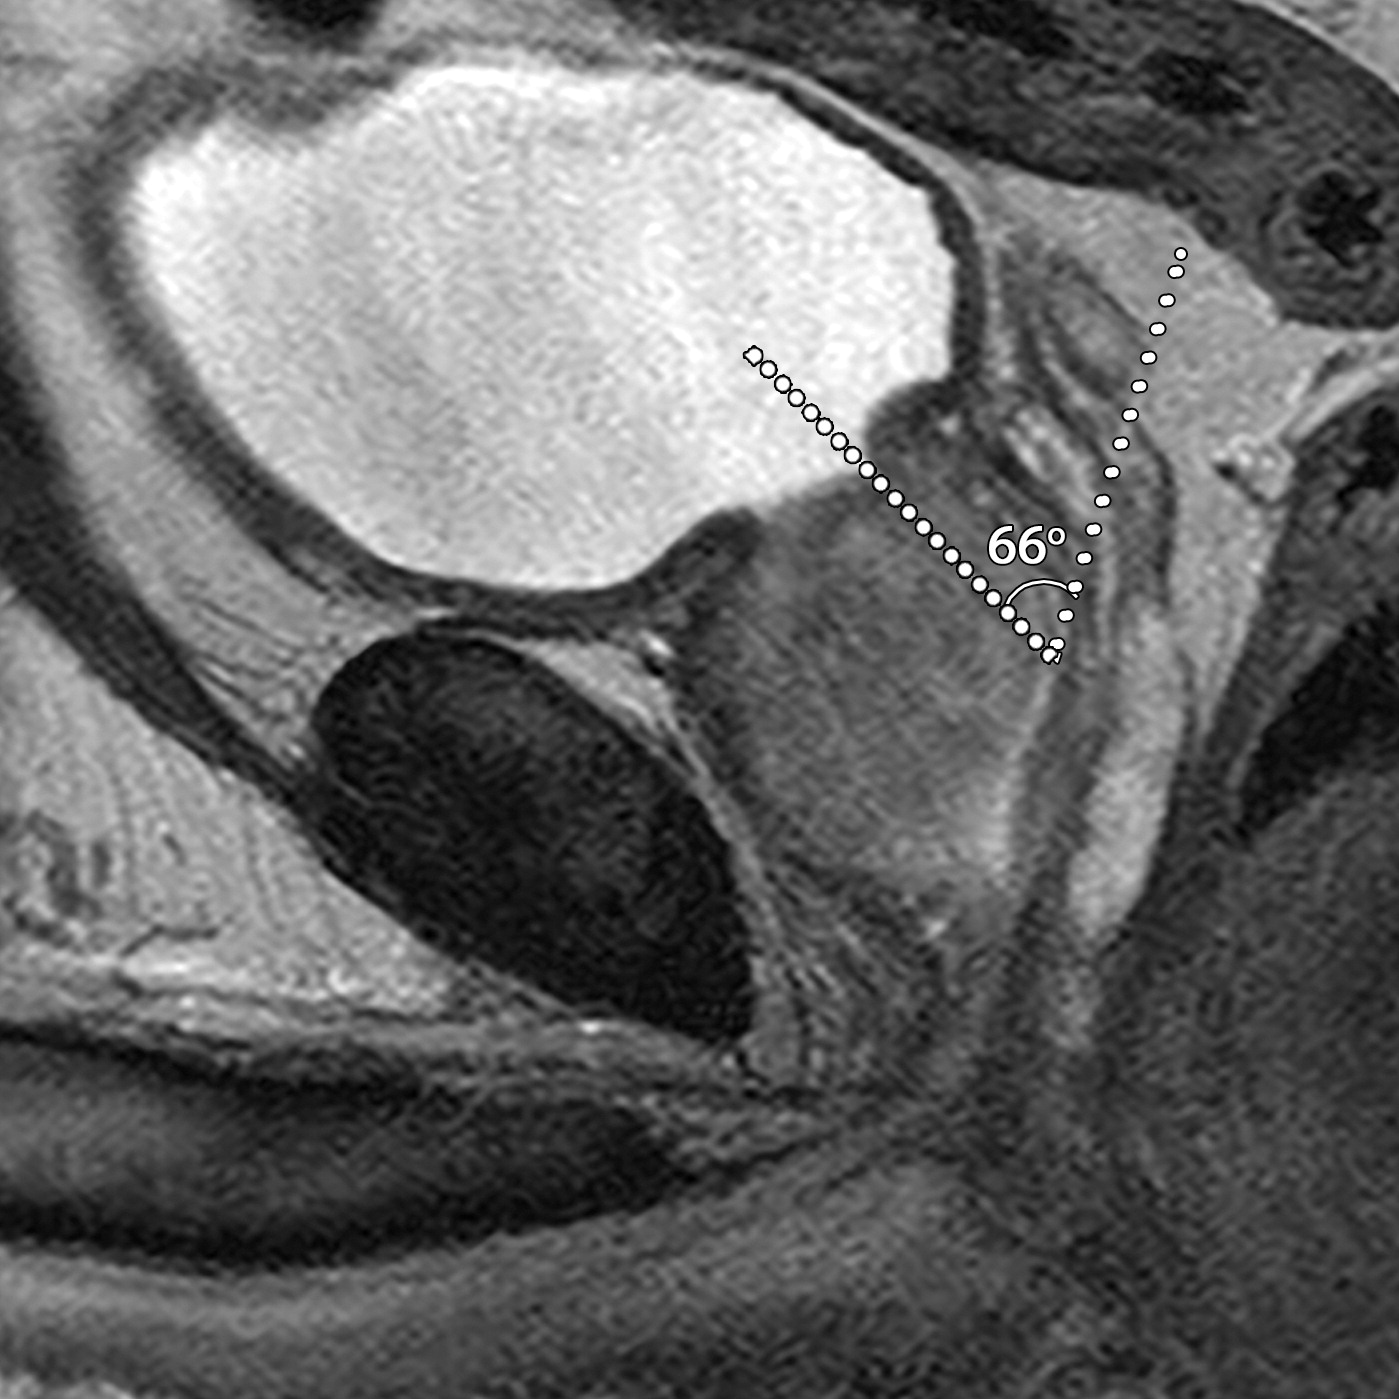

耻骨前列腺和前列腺尿道角

患者男性,39岁,良性前列腺增生,骶正中线TrueFISP MR图像显示,耻骨前列腺角从静息时的42°(a)正常增加到用力时的91°(b)。(c)67岁男性的矢状位T2加权MR图像显示前列腺-尿道角测量值为66°。